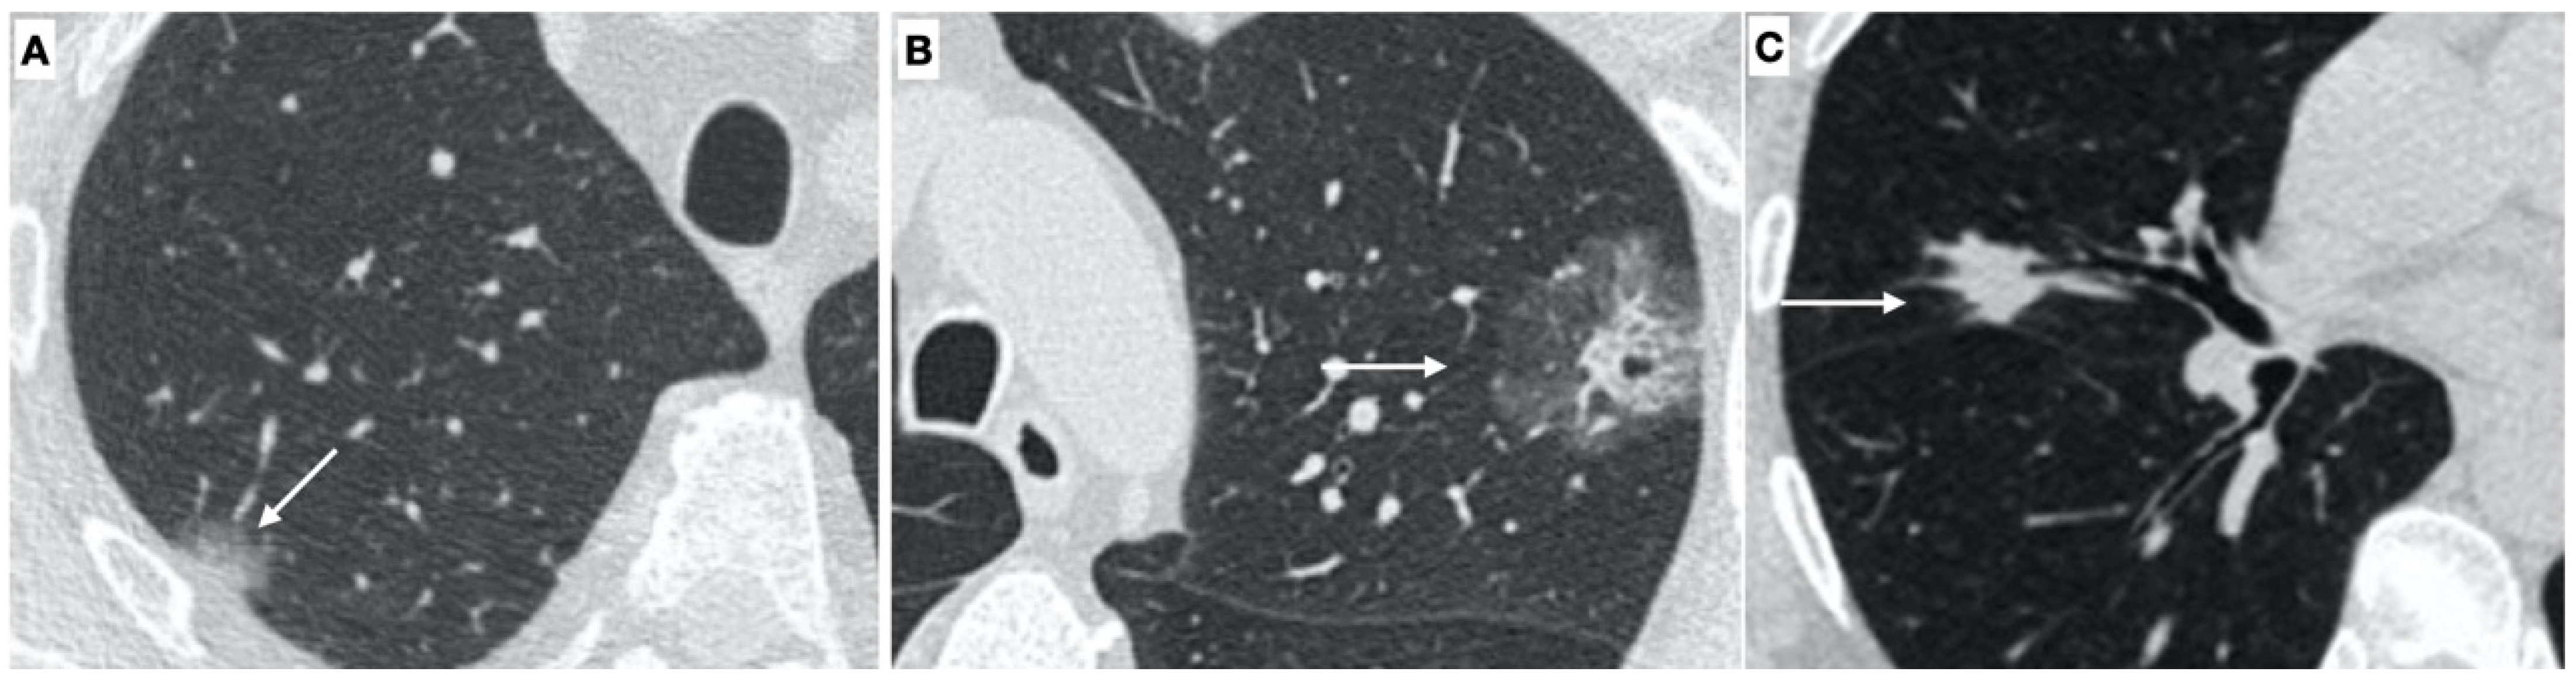

3.2. CT Findings